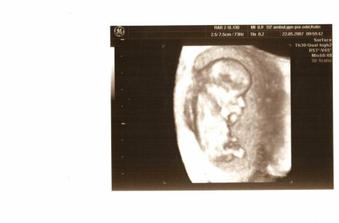

Tak takhle rosteme....1.12.2007 bychom už měli být ve třech: Tatínek Jirka, Maminka Tereza a já...Linda nebo Samuel...